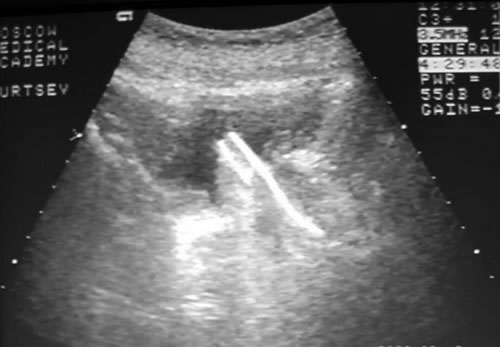

Продемонстрирована методика установки стента «Urospiral

2».

Контроль расположения спирали на рентгенограмме и при ультразвуковом

контроле непосредственно после установки.

Контроль расположения стента через 6 месяцев.